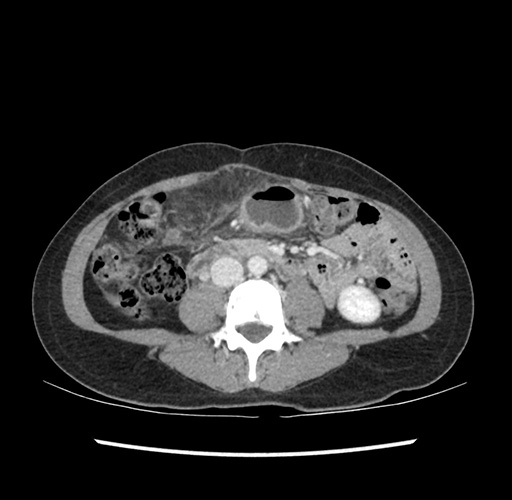

Imaging Analysis

Look through the patient's CT scan to identify any areas of concern for the necessary procedure.

Based on your CT findings, which issue(s) would give reason for "planned slowing down moment(s)" in this case?

Considering a standard left lateral sectionectomy procedure, what step(s) of the operation would you do differently in this case ?